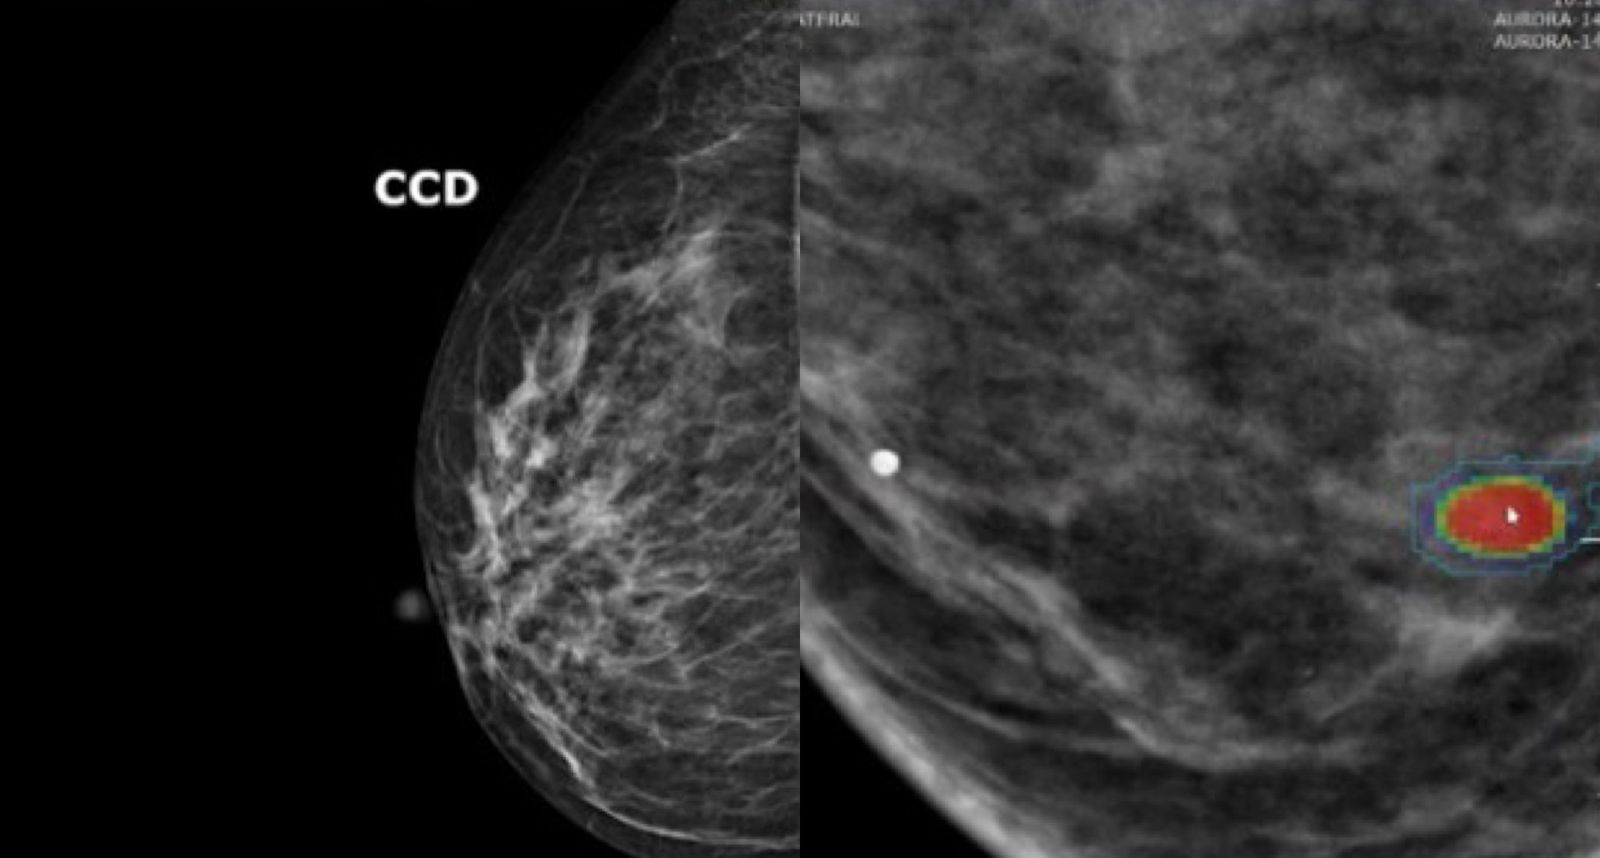

O motivo é que muitos casos de câncer de mama não são detectamos por meio da mamografia, pelo menos não em estágio inicial. Kuhl explica que em particular tumores agressivos e de crescimento rápido muitas vezes não são visíveis nas mamografias. São justamente esses tumores que matam muitas mulheres.

Agora um novo algoritmo promete reorientar a triagem: um modelo de inteligência artificial (IA) consegue avaliar com elevada precisão, simplesmente analisando dados de imagens de mamografia, o risco de uma pessoa desenvolver câncer de mama nos próximos cinco anos.

Por isso, Kuhl defende o rastreamento individualizado do câncer de mama. Afinal, a precisão da mamografia também varia significativamente de mulher para mulher: quanto mais denso o tecido mamário, maior o risco de desenvolver a doença – e pior a identificação pela mamografia. Muitas mulheres não sabem disso, conta a médica.

Para identificar quais mulheres precisam de uma RM para detecção precoce, o Consórcio Clairity (uma cooperação internacional de 46 instituições de pesquisa nos EUA, Canadá, América do Sul e Alemanha) desenvolveu o sistema de inteligência artificial Clairity Breast, que foi treinado com centenas de milhares de mamografias das Américas e da Europa.

Ao contrário dos modelos de risco tradicionais, o algoritmo não requer informações sobre histórico familiar, genética ou estilo de vida. Ele calcula a probabilidade de câncer de mama exclusivamente a partir da mamografia e categoriza as mulheres em grupos de risco com base em limiares definidos.

A IA reconhece não apenas a quantidade de tecido glandular, mas também sua textura, o que é outro parâmetro para o risco de câncer de mama. “Apenas cerca de 10% das mulheres têm esse tecido glandular extremamente denso. A grande maioria das que desenvolvem câncer de mama e recebem um diagnóstico tardio têm tecido menos denso”, afirma Kuhl.

Porém, Kuhl diz que simplesmente reduzir a idade de rastreamento não é muito eficaz. Em vez disso, ela defende uma abordagem em duas etapas. “Primeiro, mamografia para detecção precoce; em seguida, uma análise por IA deve ser realizada para determinar o risco de desenvolvimento da doença nos próximos cinco anos.”

Se o algoritmo indicar um risco particularmente alto, uma ressonância magnética deve ser oferecida, e a mamografia deixa de ser necessária para essas mulheres.